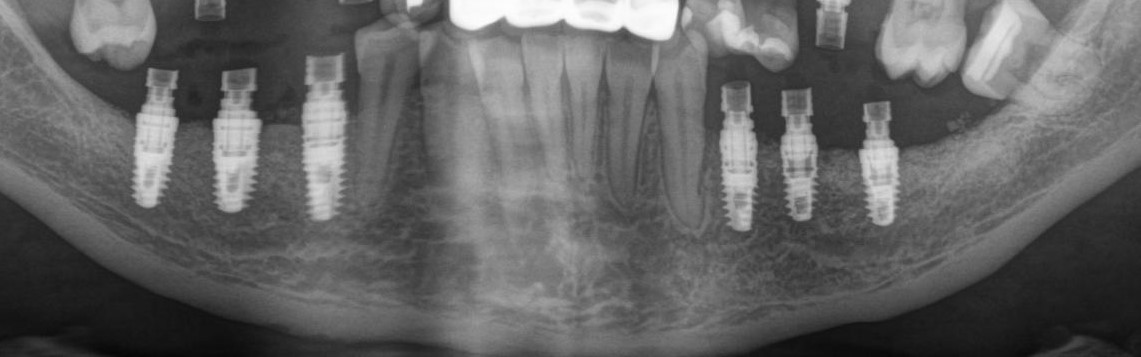

Рентгеновский снимок после операции (расщепление было проведено с двух сторон):

Снимок, сделанный через 5 месяцев после операции:

Обратите внимание, как изменился цвет кости. Она полностью восстановилась. На снимке этот участок стал белее.

Рентгеновский снимок после имплантации:

И спустя 3.5 месяца на этапе временных коронок (коронок не видно потому, что материал, из которого они изготавливаются, не рентгеноконтрастен):

Дружок в лице горизонтального зуба мудрости (на снимке справа) успешно был удалён.